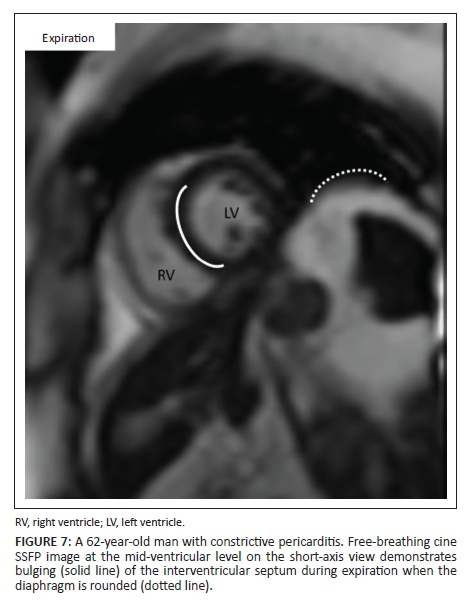

The CMR demonstrated pericardial thickening with loculated pericardial effusions as well as hyperintensity of the pericardium on the short tau inversion recovery (STIR) images (Figure 5). The free-breathing cine SSFP images demonstrated 'septal bounce', confirming constrictive pericarditis (Figures 6 and 7).

During expiration, there is decreased venous return to the right ventricle, and the pressure in the left ventricle increases relative to that of the right ventricle. This differential causes the septum to move towards the right ventricle reassuming its normal curvature (Figure 7). On the free-breathing SSFP images, these physiological changes can be visualised and accentuated by asking the patient to take in a deep breath during the acquisition of the short-axis cine images.9

• For constrictive pericarditis, real-time free-breathing images are useful to assess for septal bounce (Figures 6 and 7). This is usually done as a single slice at a mid-ventricle level.1